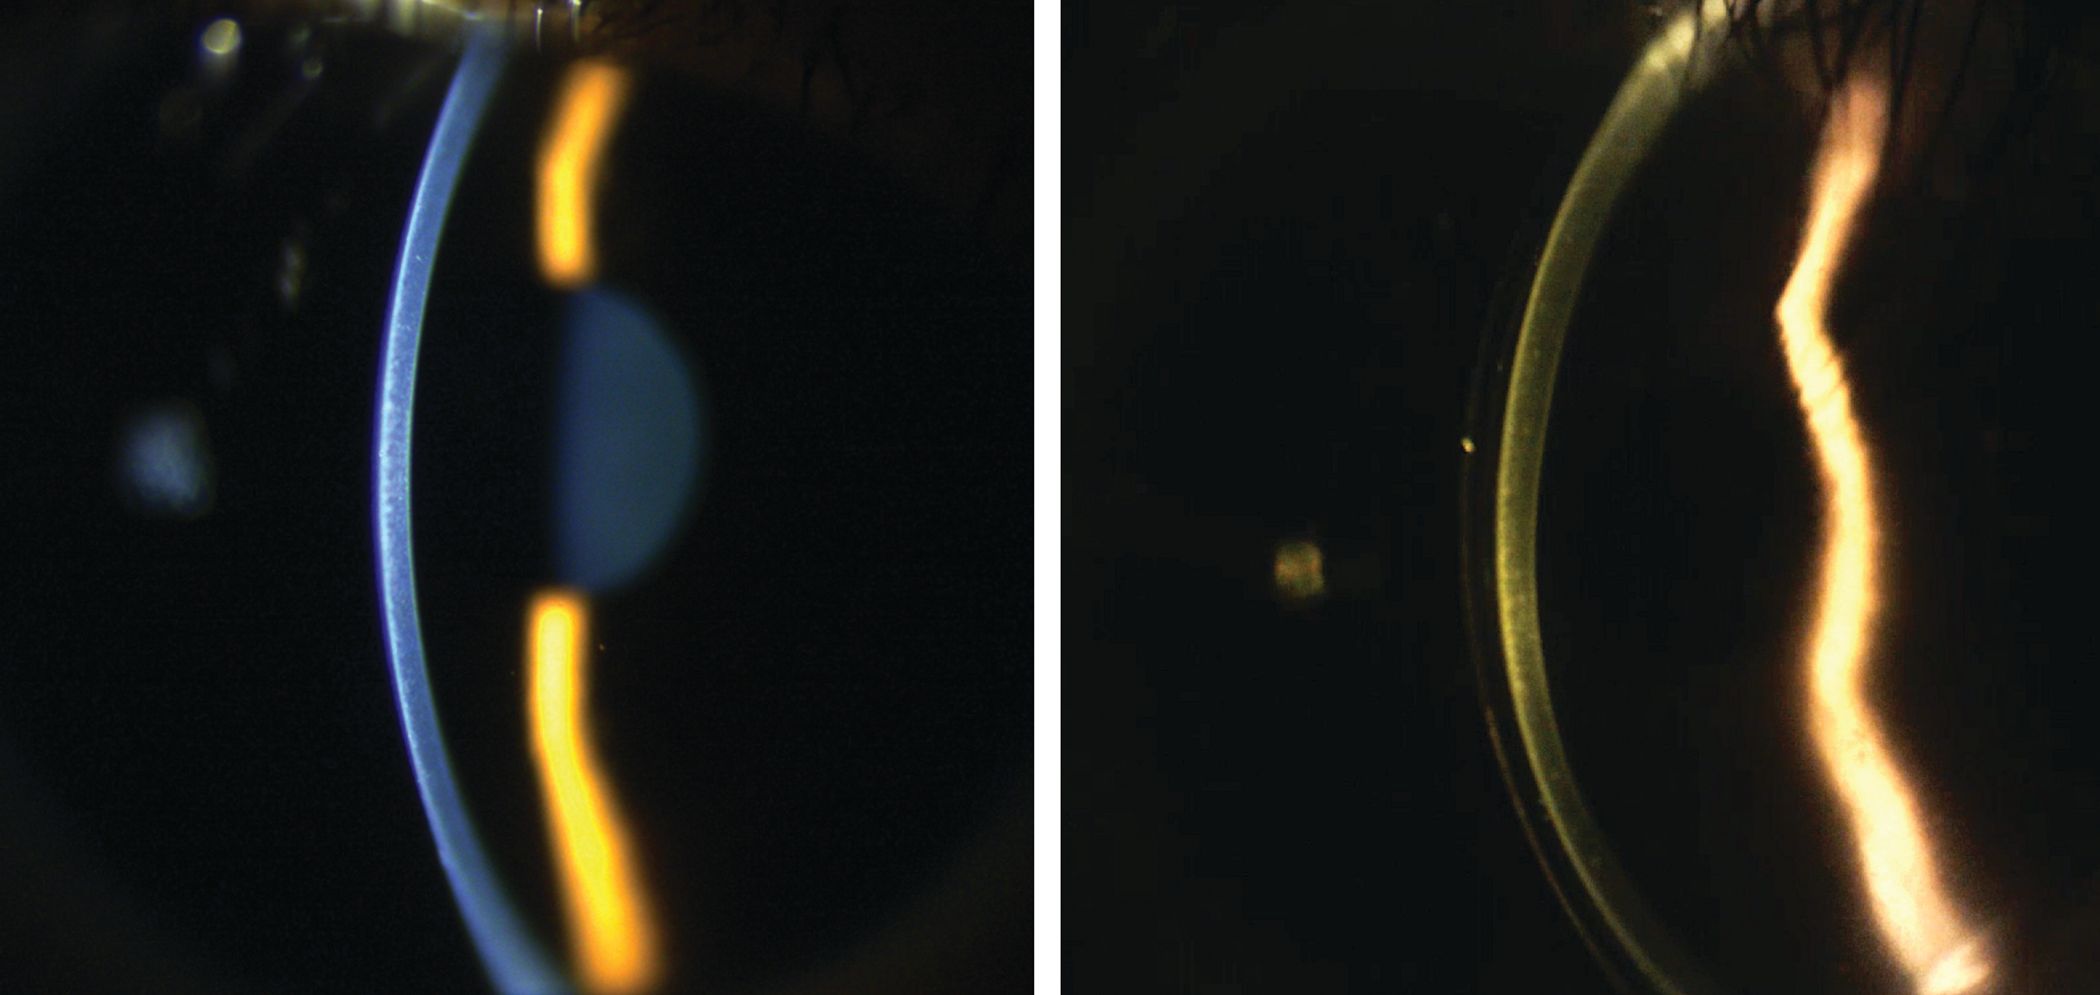

Individuals often have questions about their candidacy for certain implants and how the various mechanisms of action work.